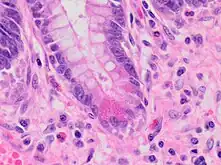

| A micrograph demonstrating cryptitis, a microscopic correlate of colitis. H&E stain. | |

An important investigation in the assessment of colitis is biopsy for histopathology. A very small piece of tissue (usually about 2mm) is removed from the bowel mucosa during endoscopy and examined under the microscope by a histopathologist. A biopsy report generally does not state the diagnosis, but should state any presence of chronic colitis, give an indication of disease activity, as well as state the presence of any epithelial damage (erosions and ulcerations).[4]

Histopathology findings generally associated with chronic colitis include:[4]

Other findings include basal plasmacytosis and mucin depletion.[4] Histopathology findings generally associated with active colitis include:[4]

Neutrophilic cryptitis (neutrophils within crypt epithelium)

Crypt abscesses (luminal neutrophilic aggregates)

Gland destruction

Ulceration (seen here as absence of epithelium, and granulation tissue with many fibroblasts)